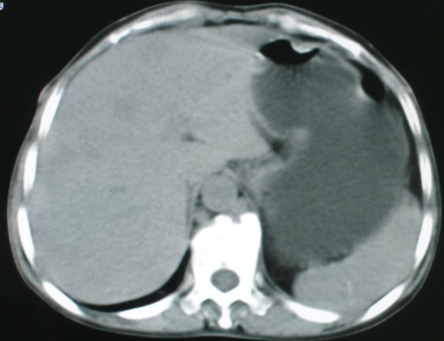

以下是引用zsl6918在2008-11-4 19:14:00的发言:[br]多发转移性改变,子宫改变不除外为原发灶